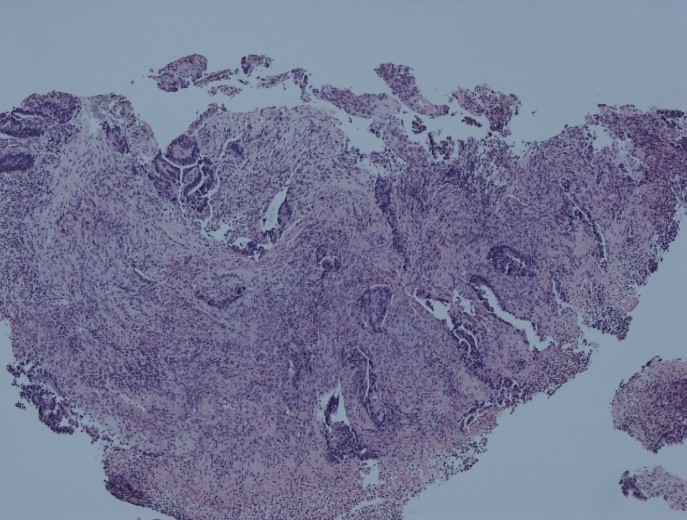

Surgical resection specimens (larger pieces of diseased tissue) are examined, described and dissected by both medical histopathologists and healthcare scientists, with representative areas of individual specimens sampled and processed through the laboratory. The samples are stained to assess any significant changes in the structure of the tissue.

Diagnosis is usually made on a glass side using a light microscope but, increasingly, digital pathology is being utilised for routine diagnostic histopathology. In digital pathology, images of the glass slide are created and captured with a scanning device to provide a high-resolution image that can be viewed on a computer screen or mobile device.

Cells that have grown normally have a uniform and organised appearance. By contrast, abnormal cells show a different range of features, a deeper colour on staining and a disorganised growth pattern. The bowel is made up of tissue layers, and when these abnormal cells grow in the wrong areas, this is known as cancer. To aid diagnosis, further investigations, using genetic testing or immunohistochemistry (a technique that makes proteins visible and helps to identify whether the patient has abnormal mismatch CASE repair genes), are performed. Mismatch repair genes are responsible for correcting any errors that are made when DNA is copied within a normal cell. Cells with abnormal mismatch repair genes build up many DNA mutations, which can lead to bowel cancer developing. Knowing whether there are abnormalities in the mismatch repair genes helps to exclude an inherited disorder called Lynch syndrome. It can also predict how the tumour will respond to any treatments that are planned for the patient.